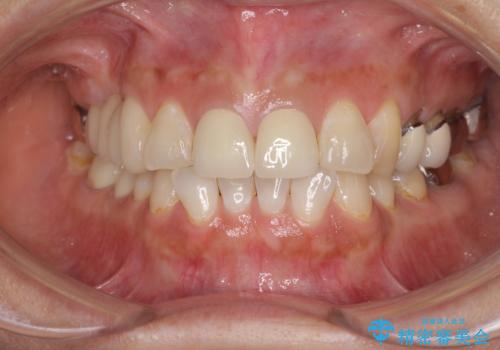

前歯2本を同時に処置したことにより、色合いも形態もバランスの取れた仕上がりとすることができました。

10年近く人にあまり見られないようにしていた前歯でしたが、人目を気にせず笑えるようになり、患者様には大変満足していただきました。